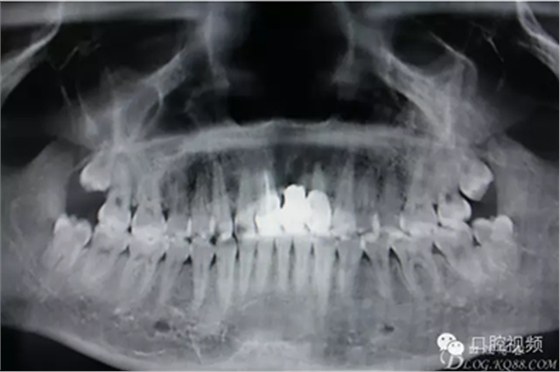

圖2.全景片影像資料檢查:21牙槽骨幾乎完全吸收。橋體牙冠與牙槽嵴相接觸